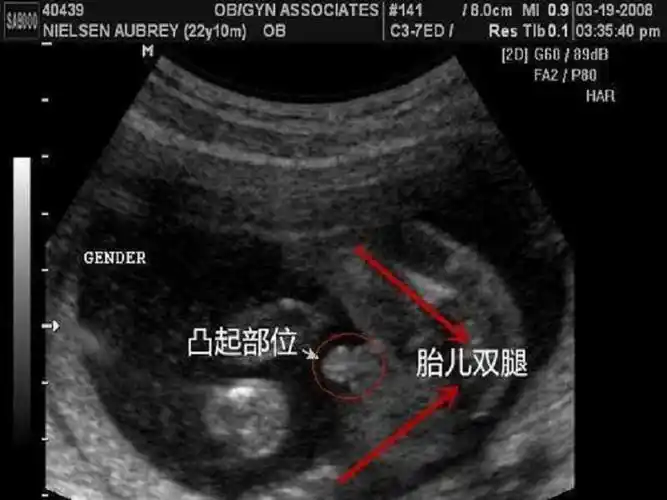

怀孕十二周

2,男宝宝的屁股位置会微微上翘,后背脊柱成圆弧状,因为要留空间发育

胎儿十二周发育都有哪些具体的变化有没有图片做对比

人类胎儿- 12周